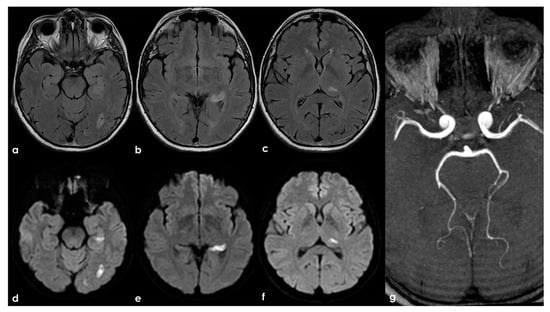

Figure 2.

Brain MRI (axial FLAIR in panels (a–d), coronal T2W in panels (a–g), and axial T2W in panel (h)) showing small punctate white-matter hyperintensities in the centrum semiovale, with a trend to watershed distribution (panel (d)), and a mild increase in enlarged perivascular spaces in the subcortical white matter (panels (e–h)).